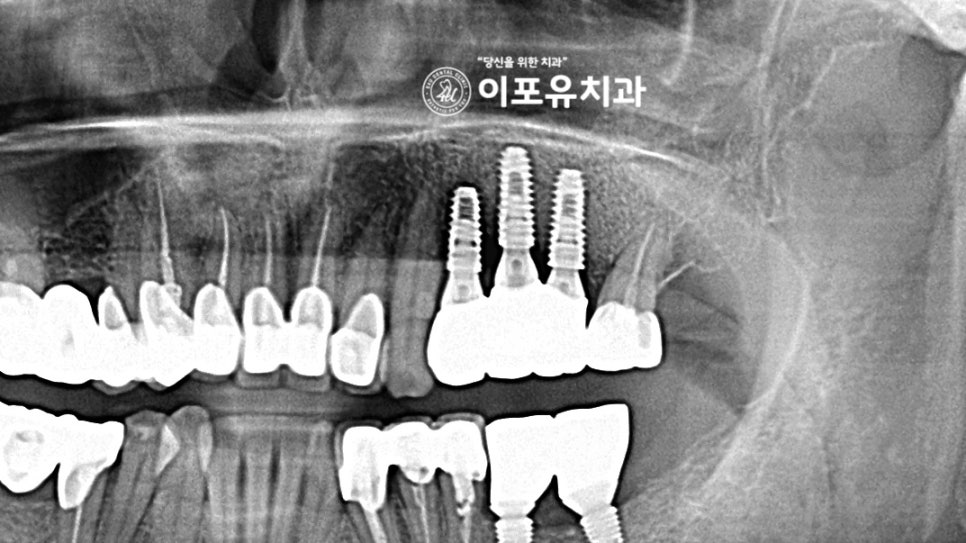

파노라마 사진을 보면

구치부 치아 3곳이 빠져 있는 것이 관찰되는데요.

이와 더불어 구강 전체에서

다량의 치석을 동반한 치주 질환이 확인됩니다.

어금니 상실도 심한 잇몸 염증으로 인해

일어난 것으로 보입니다.

이전과는 달리 빼곡하게 보강된

이식재의 모습이 관찰됩니다.

골 유착이 안정적으로 이뤄진 것을 볼 수 있는데요.

주변 조직, 인접치와의

거리 등을 고려하여 픽스쳐를 심는 것이 중요합니다.